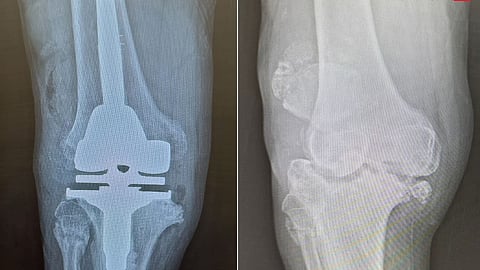

وقال د.عبدالله الشهراني استشاري جراحة العظام واستبدال المفاصل الصناعية، رئيس الفريق الطبي المعالج، أن المراجع جاء إلى المستشفى وهو يشكو من أعراض كالآلام والتورم وتغير شكل الركبة، بالإضافة إلى صعوبة الحركة، وأجريت له سلسلة من الفحوصات الدقيقة، كالتصوير بالرنين المغناطيسي والأشعة السينية، وبينت النتائج وجود تآكل في عظمتى المفصل، وخلل في حركة عظمة رأس الركبة مع الخشونة والاحتكاك الحاد، وكذلك ارتخاء شديد في أربطة الركبة الجانبية، وتلف غضاريف المفصل.

وقام الفريق الطبي بدراسة الحالة بدقة على ضوء نتائج الفحوصات، وخلص إلى أن هناك ضرورة لإجراء عملية لاستبدال المفصل، بآخر صناعي يتوافق مع معطيات التشخيص الطبي للحالة، وبعد اتخاذ الترتيبات والتحضيرات اللازمة أجريت له عملية تم فيها، استبدال مفصل الركبة بآخر صناعي يناسب الحالة، بالاستعانة بأحدث الأجهزة الطبية، وتكللت العملية التي استمرت لمدة "90" دقيقة، ولله الحمد بالنجاح، وتمكن المراجع من المشي على قدميه بعد "5" ساعات من العملية، وغادر المستشفى بحالة صحية جيدة بعد "7" أيام.